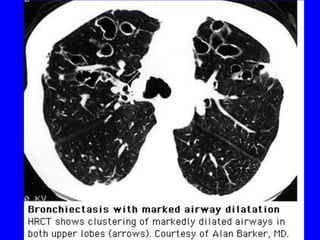

HRCT

• Sensitivitiy ~97%

• Findings

–   Airway dilation

–   Lack of tapering of bronchi

–   Bronchial wall thickening

–   Mucopurulent plugs or debris

–   Cyst

–   Pneumonia, LAP, emphysema

• Distributions

– Upper lobe

– Central distribution

Radiol Clin N Am 43(2005) 513-542